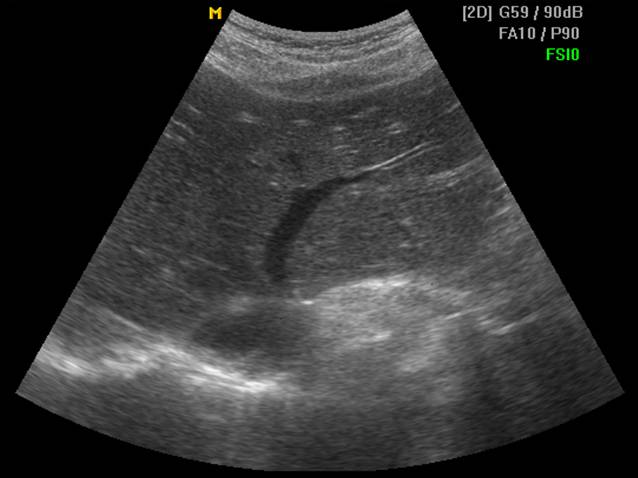

肝静脉分三支即肝左静脉、肝中静脉和肝右静脉,三大肝静脉汇入下腔静脉位于膈肌下方约1cm处,称第二肝门。

肝左静脉和肝中静脉可先合成短干,然后汇入下腔静脉。

(二)通过肝静脉进行分叶

肝静脉主干在叶间裂或段间裂内行走,易于超声显示,最便于进行肝脏分叶、分段。

2. 肝中静脉行走于正中裂的后半部和尾状叶内,右半肝与左半肝分界

肝左右叶的超声分界标志(肝中静脉)

肝左右叶的超声分界标志(胆囊切迹-下腔静脉左缘连线)